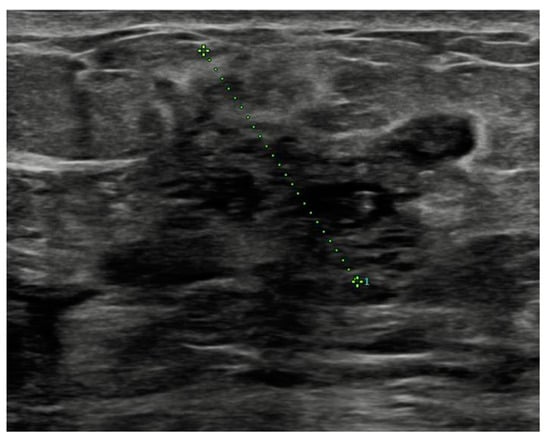

Before surgery, all patients underwent breast ultrasound to assess the presence of an abscess or fistula. Regarding clinical and radiological presentation, 12 patients presented with an abscess in the form of a painful and tender breast mass, with tense and reddened skin but no cutaneous fistula, confirmed by ultrasound (Figure 1, Figure 2 and Figure 3); two patients presented with an abscess associated with periareolar fistula (Figure 4), visible on breast ultrasound; five patients showed signs of a past abscess with negative preoperative ultrasound findings, and among them, one had a fistulous tract without purulent discharge (Table 1). The location of abscesses, fistulas, and their sequelae was the periareolar area in all patients. Additionally, four patients presented with bilateral symptoms. For patients with active abscesses at surgery, the mean size of the abscess cavity was 28.7 mm.

Figure 3. Abscess with an overall extent of 6 cm × 3.5 cm.